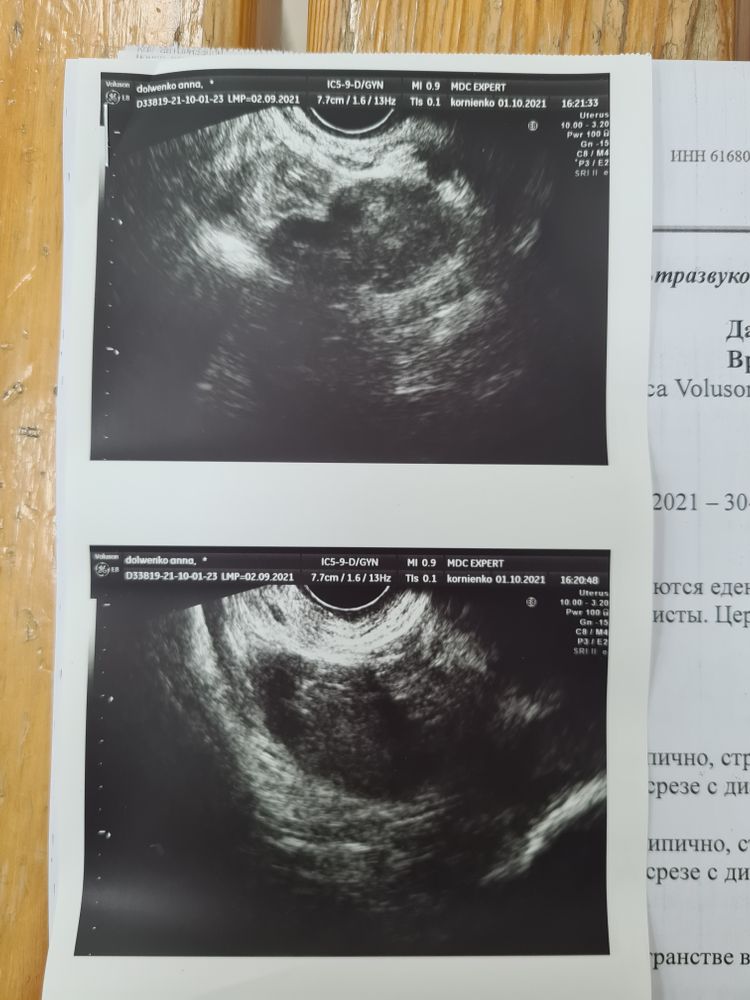

Сегодня 30 дц, из 34х, вчера начал болеть живот и левый яичник, сходила на узи, сказали чуть ли не скорую вызывать, неужели все так страшно по узи?

Анна, интересная овуляция, без доминантного фолликула,а если она прошла,то где жёлтое тело и откуда свободная жидкость??Вы гинеколога не пробовали поменять???

Фантик, сегодня пойду на узи повторно, если жёлтое тело есть, значит была овуляция. Просто в этом цикле я не отслеживала вообще доминантный фолликул, а пошла на узи потому что живот стал болеть